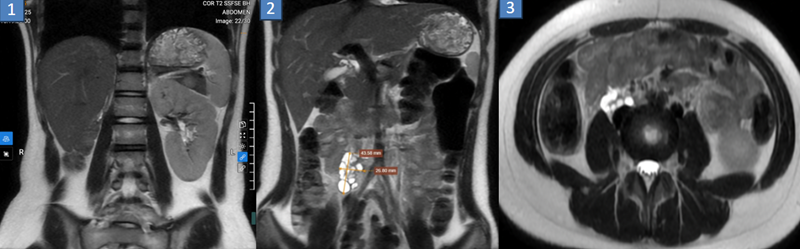

Kết quả chụp MRI không quan sát thấy thận trong hố thận phải. Vị̣ trí khoang sau phúc mạc bên phải ngang mức L3-4, phía trước cơ thắt lưng chậu có cấu trúc nghi thận kích thước 27x44mm, kèm nhiều nang nhỏ

Kết quả siêu âm ổ bụng và MRI tiểu khung ghi nhận: hình ảnh tử cung đôi hoàn toàn; vách ngăn âm đạo kèm ứ đọng dịch máu trong nửa phải âm đạo; thận phải loạn sản đa nang, lạc chỗ.